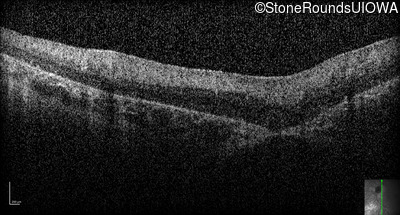

Optical Coherence Tomography - Right -

No Light Perception

Exemplar

Expanded OCT Stack

×